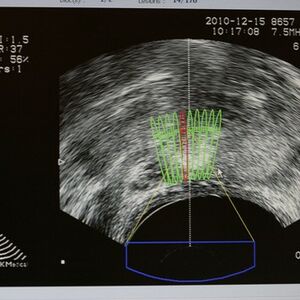

“Kada se rano otkrije, rak prostate se može izlečiti. Muškarci stariji od 50 godina treba jedanput godišnje da urade PSA (prostata specifični antigen) i da odu na pregled kod urologa, kao i pre 45. godine, ukoliko u porodici imaju slučajeve ovog karcinoma (otac, ujak, stric),” navodi prof. dr Zoran Džamić, profesor na Medicinskom fakultetu u Beogradu i direktor Klinike za urologiju Univerzitetskog kliničkog Centra Srbije. “Rak prostate retko daje rane simptome, ali se može javiti poremećaj u kvalitetu mokrenja - otežano i učestalo mokrenje, noćno mokrenje, smanjenje jačine mlaza, kao i krv u mokraći. U uznapredovaloj fazi bolesti javljaju se bolovi u kostima, pre svega karlice. Povišena vrednost PSA u krvi ne mora da znači da muškarac ima rak prostate, već to može biti posledica benignog uvećanja prostate ili zapaljenskog procesa, i zato je važno da urolog obavi pregled (digitorektalni pregled, ultrazvuk) i proceni rizik za razvoj raka prostate. Ukoliko se posumnja na postojanje raka, radi se biopsija prostate. Ako se histopatološki potvrdi rak, procenjuje se proširenost bolesti. Pacijent se upućuje konzilijumu, gde iskusni kliničari donose odluku o najboljem načinu lečenja.”- objašnjava prof. Džamić.